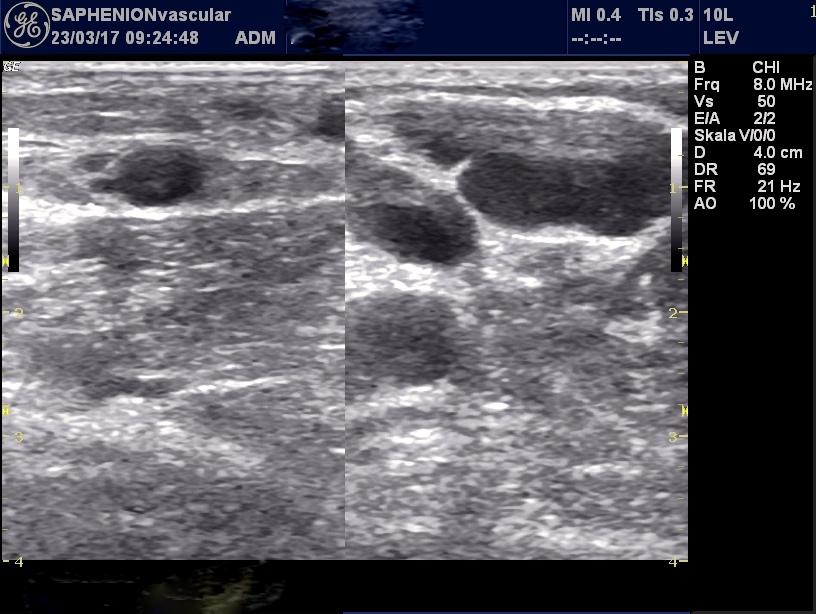

Post operative Sonographie nach VenaSeal® der V. saphena parva – krossennahe Aneurysmata und ektatische Venen aus der Giacomini – Vene gespeist und in die Parvakrosse mündend…

Post-operative ultrasound after VenaSeal of SSV – nearly the junction we found aneurysmatic and ecstatic side branches to the popliteal junction coming from the Giacomini`s vein

Intra operative Sonographie – zunächst direkte Punktion der Aneurysmata und ektatischen Venenabschnitte mittels Minikatheter ultraschallgestützt – Abgabe von 2 -3 Tropfen VenaSeal in diese Abschnitte und Wahrung des Therapieprotokolls (alle 2 – 3 cm = 0,09ml Kleber) – danach Mikroschaum der Seitenastvaricosis

Intra-operative ultrasound – at first direct punction of aneurysmatic and ectatic parts of side branches ultrasound-guided – injection of 2 – 3 ml of glue into these parts with keeping the therapy protocol ( all 2 – 3 cm one drop with 0,09 ml of glue) – after this microfoam of normal side branches.